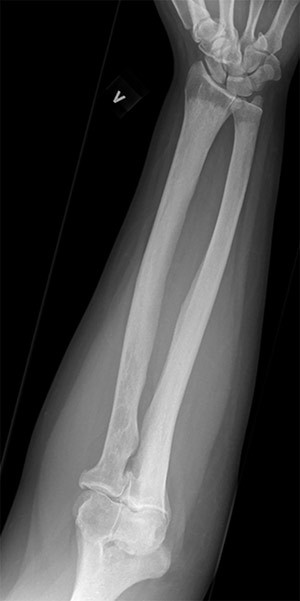

Røntgenundersøkelse av de lange rørknoklene viste symmetrisk utbredt sklerose i diafyser og metafyser, med utsparing av epifysene i radius, ulna, femur og tibia (fig 5). I tillegg var det tegn til periostitt, mest uttalt i femur og i tibia. Ved skjelettscintigrafi var det kraftig aktivitetsopptak i distale del av femur, proksimale og distale del av tibia, distale del av radius og i maksillen bilateralt (fig 6). Endokrinolog fant ikke holdepunkter for diabetes insipidus eller andre endokrine forstyrrelser.